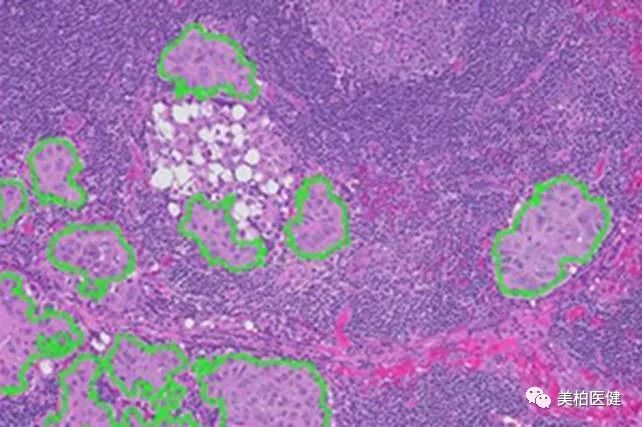

histoSēK™则可以自动识别和量化目标组织学区域,即可能含有有害生长的扫描载玻片区域,并且拥有显微切割,坏死区域量化或肿瘤负荷测量功能。

▲ 图片来源:Inspirata